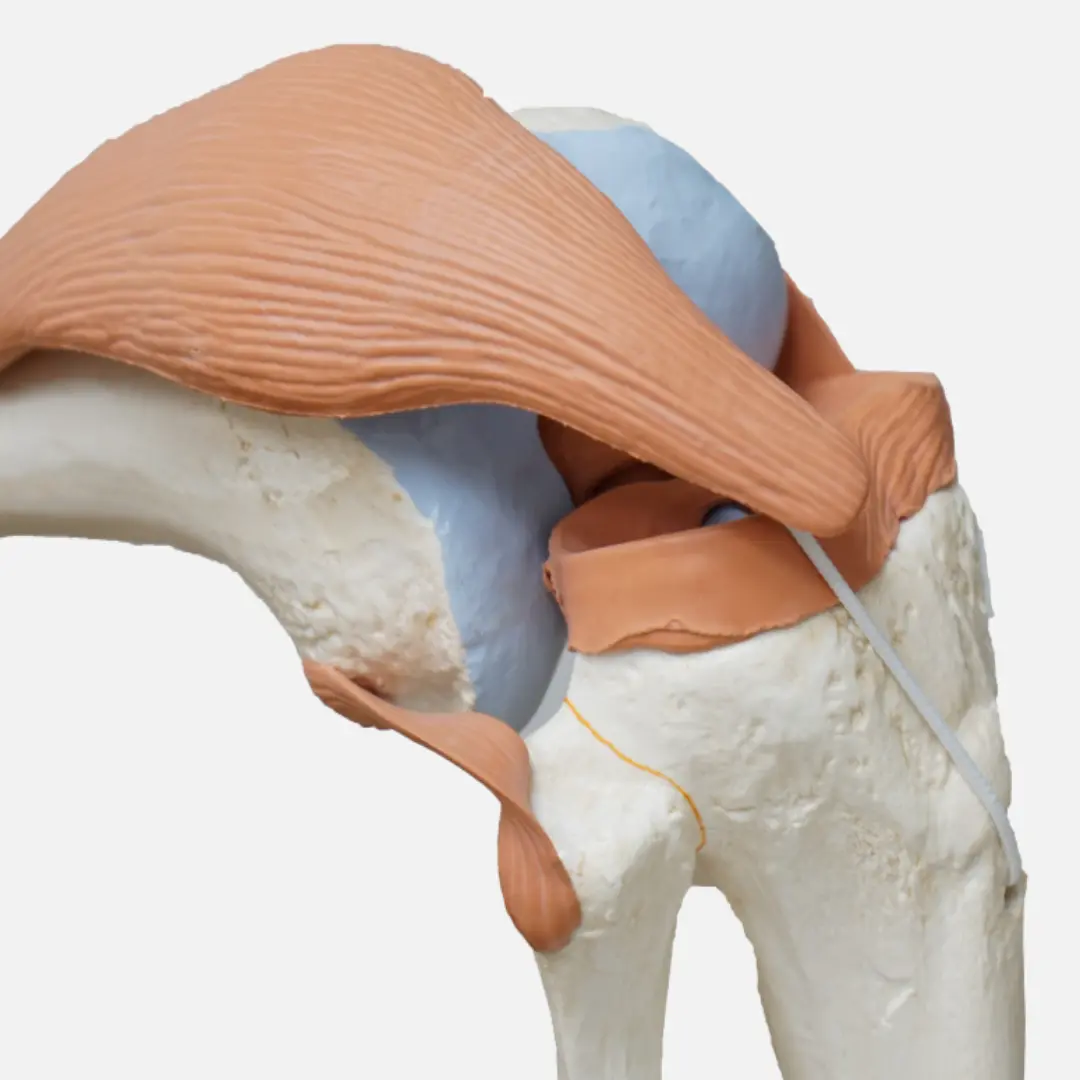

- 적절한 운동: 관절 주변 근육을 강화하는 운동은 관절을 지지하고 안정화시켜 통증을 줄이는 데 도움이 돼요. 수영, 걷기, 요가 등이 관절에 부담을 덜 주면서 근력을 강화하는 좋은 운동입니다.